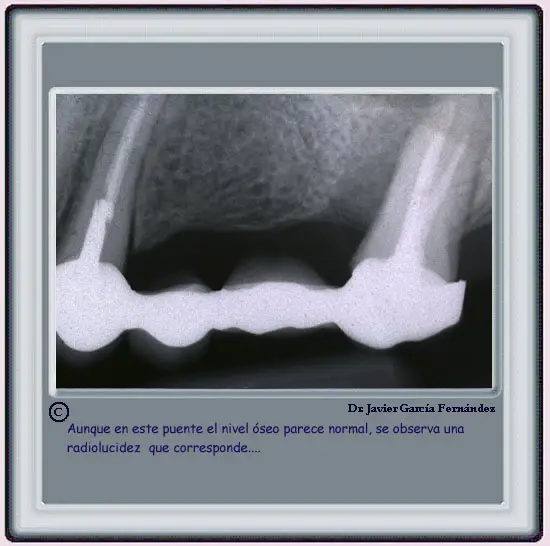

EXAMEN RADIOLOGICO